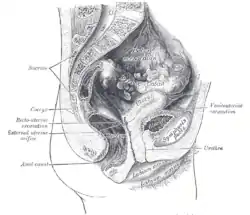

Image showing different structures around and relating to the human uterus | |

Structure

The uterus is located within the pelvic region immediately behind and almost overlying the bladder, and in front of the sigmoid colon. The human uterus is pear-shaped and about 7.6 cm (3.0 in) long, 4.5 cm (1.8 in) broad (side to side), and 3.0 cm (1.2 in) thick.[1][2] A typical adult uterus weighs about 60 grams. The uterus can be divided anatomically into four regions: the fundus – the uppermost rounded portion of the uterus, the corpus (body), the cervix, and the cervical canal. The cervix protrudes into the vagina. The uterus is held in position within the pelvis by ligaments, which are part of the endopelvic fascia. These ligaments include the pubocervical ligaments, the cardinal ligaments, and the uterosacral ligaments. It is covered by a sheet-like fold of peritoneum, the broad ligament.[3]

From outside to inside, regions of the uterus include:

- Cervix uteri – "neck of uterus"

- External orifice of the uterus

- Cervical canal

- Internal orifice of the uterus

- Body (Latin: Corpus)

- Uterine cavity

- Fundus

Fetus in utero, between fifth and sixth months. Female pelvis and its contents, seen from above and in front

Female pelvis and its contents, seen from above and in front The arteries of the internal organs of generation of the female, seen from behind